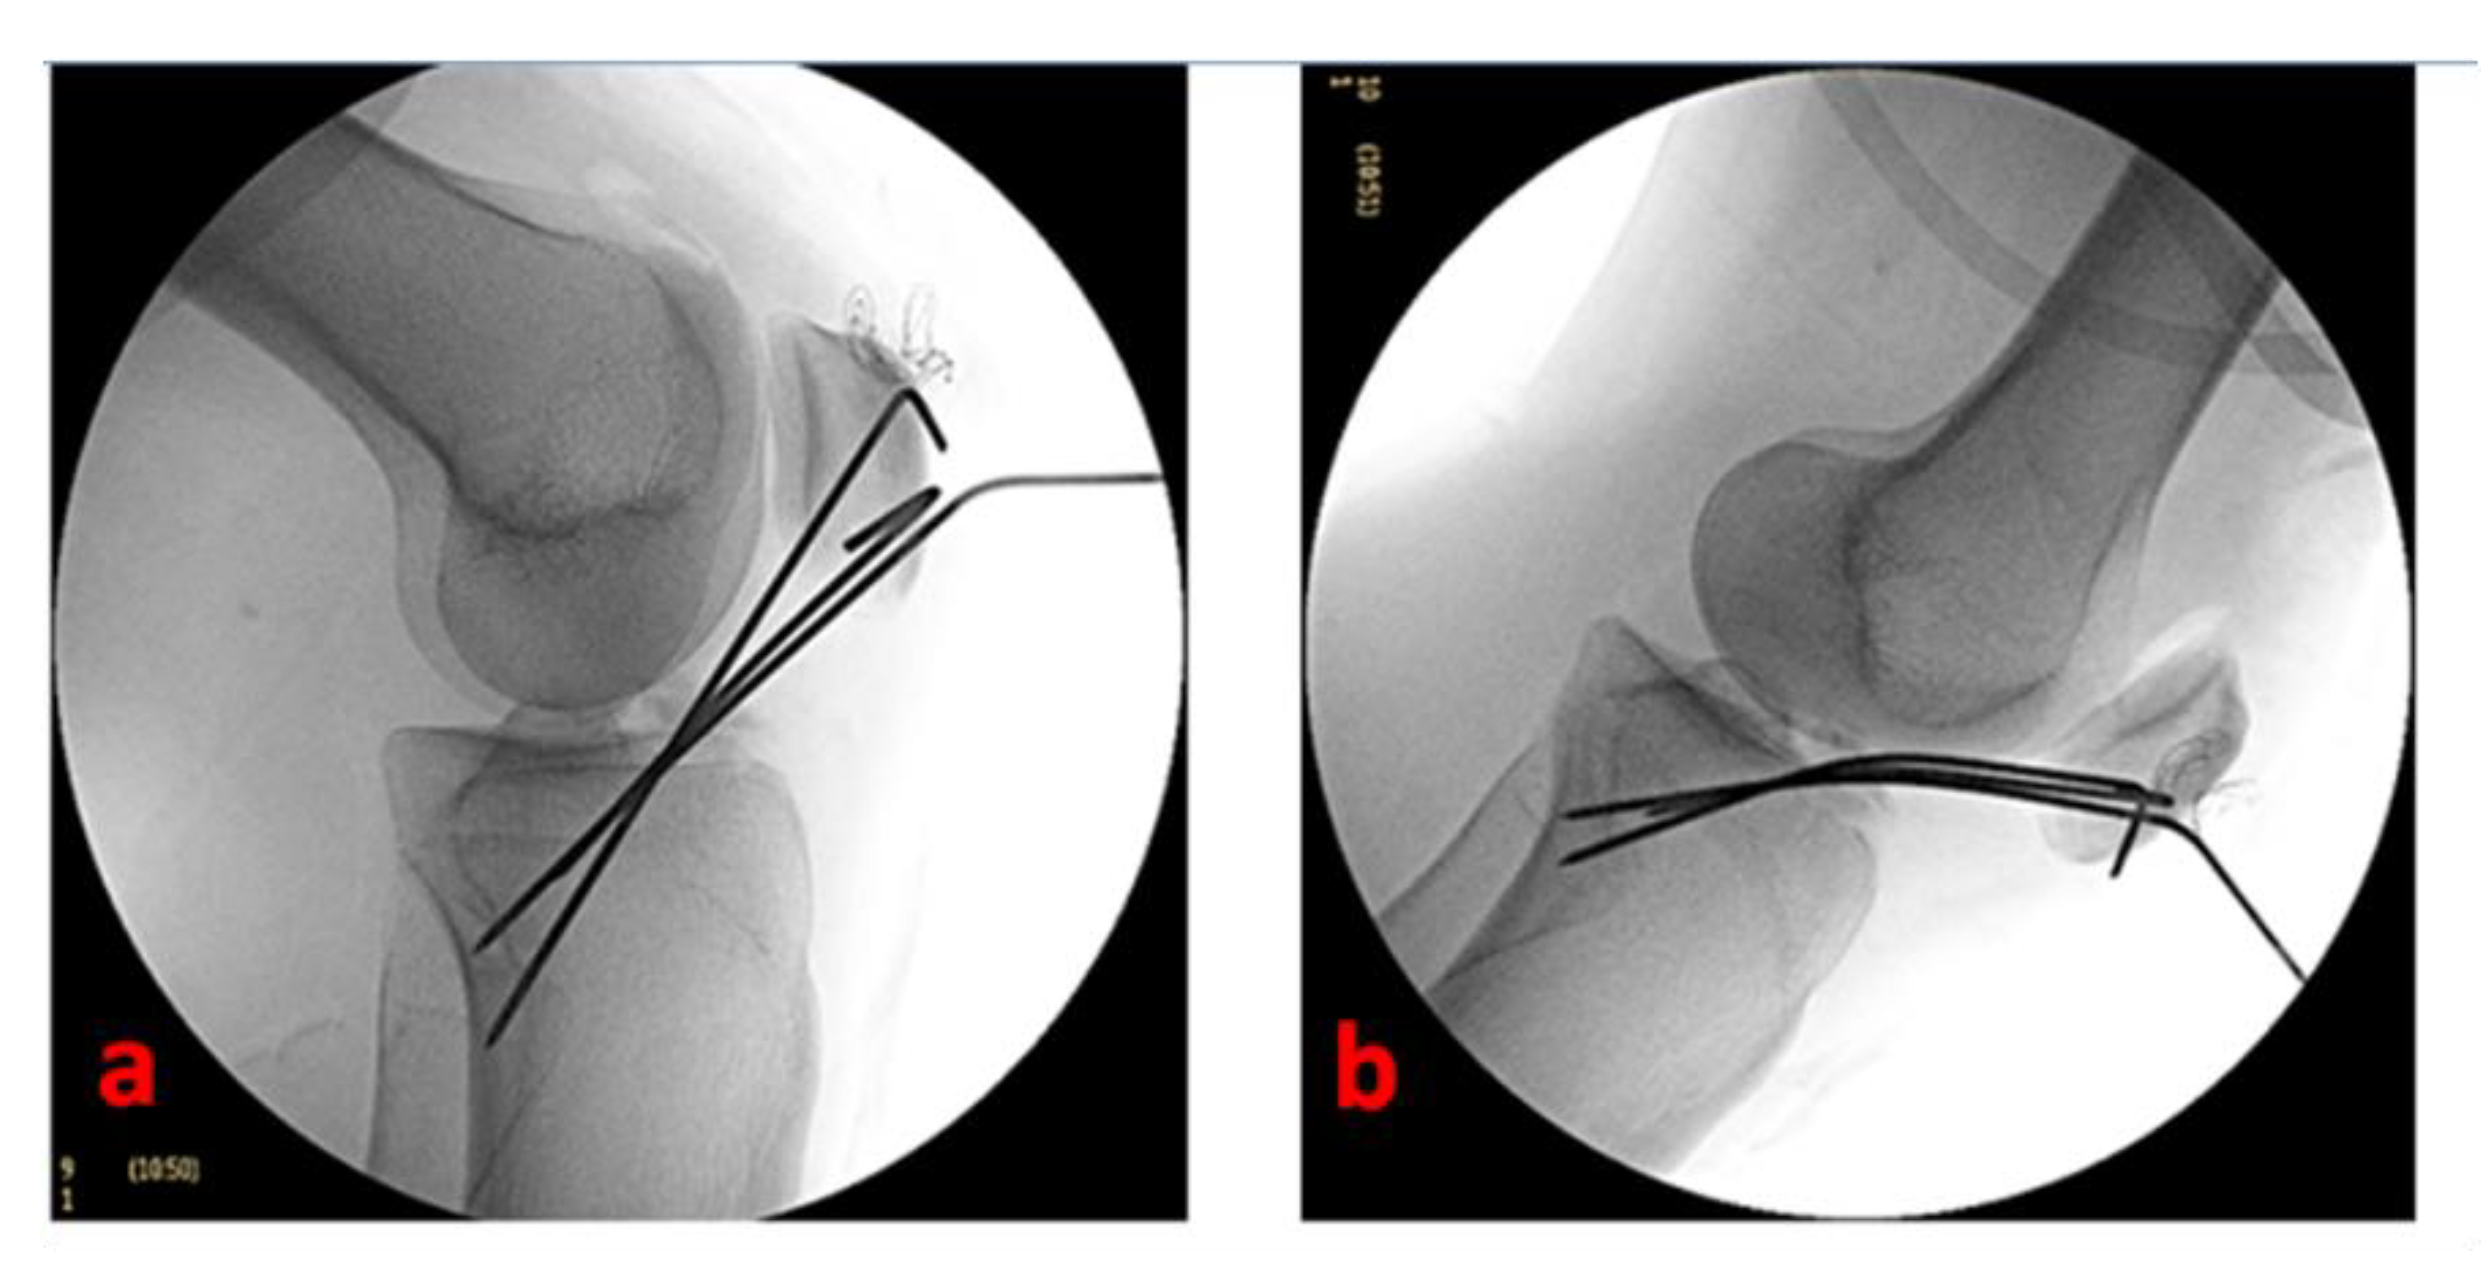

Under arthroscopic and fluoroscopic visualization, we completely extend the knee to confirm the effectiveness of reduction and stability. The Kirschner wires are externally cut (by maintaining a 2–3 cm straight external portion—essential for the subsequent removal) and curved (Figure 4).

Figure 4.

Fluoroscopic control of fracture reduction and osteosynthesis devices positioning of the left knee of a 16-year-old female patient with the knee flexed to 90° (a) and the knee completely extended (b).

At this stage, the tourniquet is let down, the hemostasis performed, and the arthroscopic portals sutured. A compressive bandage and a long-leg cast at 30° of knee flexion (with the K wires anchored to the cast) are applied.